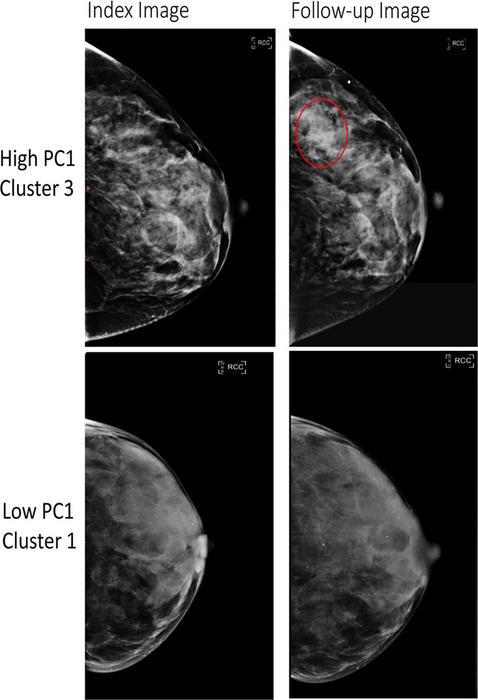

In a groundbreaking study published in the esteemed journal Radiology, researchers have unveiled six distinct breast parenchymal texture patterns that may signal an increased risk of developing breast cancer. This large-scale investigation leverages advanced radiomic techniques applied to mammographic images, marking a significant leap forward in breast cancer risk stratification beyond traditional breast density measures.

The study, spearheaded by a multidisciplinary team including epidemiologists and radiologists, analyzed over 30,000 mammograms from women with no prior history of breast cancer, drawn from three diverse screening cohorts. Utilizing radiomics—a cutting-edge computational approach that extracts and quantifies intricate patterns from medical images invisible to the naked eye—the researchers identified 390 quantitative imaging features. These features were then distilled into six prominent phenotypes or texture patterns that epitomize variations in breast parenchymal architecture.

To validate their findings, the team examined these phenotypes in an independent cohort exceeding 3,500 women, including those who later developed invasive breast cancer and those who remained cancer-free. Strikingly, the existence of specific radiomic phenotypes correlated strongly with an elevated risk of invasive disease. These associations persisted across racial lines, providing a robust framework for predicting cancer risk with potential implications for personalized screening programs.

Beyond risk prediction, the phenotypes also showed promise in forecasting diagnostic challenges such as false-negative mammograms—where cancer lesions are missed during routine screening—and interval cancers, which are diagnosed between scheduled mammograms and often have worse prognoses. Being able to anticipate these diagnostic blind spots could revolutionize follow-up protocols and preventive interventions.